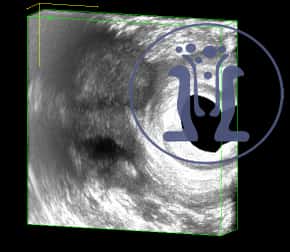

Το ενδοπρωκτικό υπερηχογράφημα έδειξε επέκταση μέσα στους σφιγκτήρες του πρωκτού χωρίς πρωκτικό στόμιο.